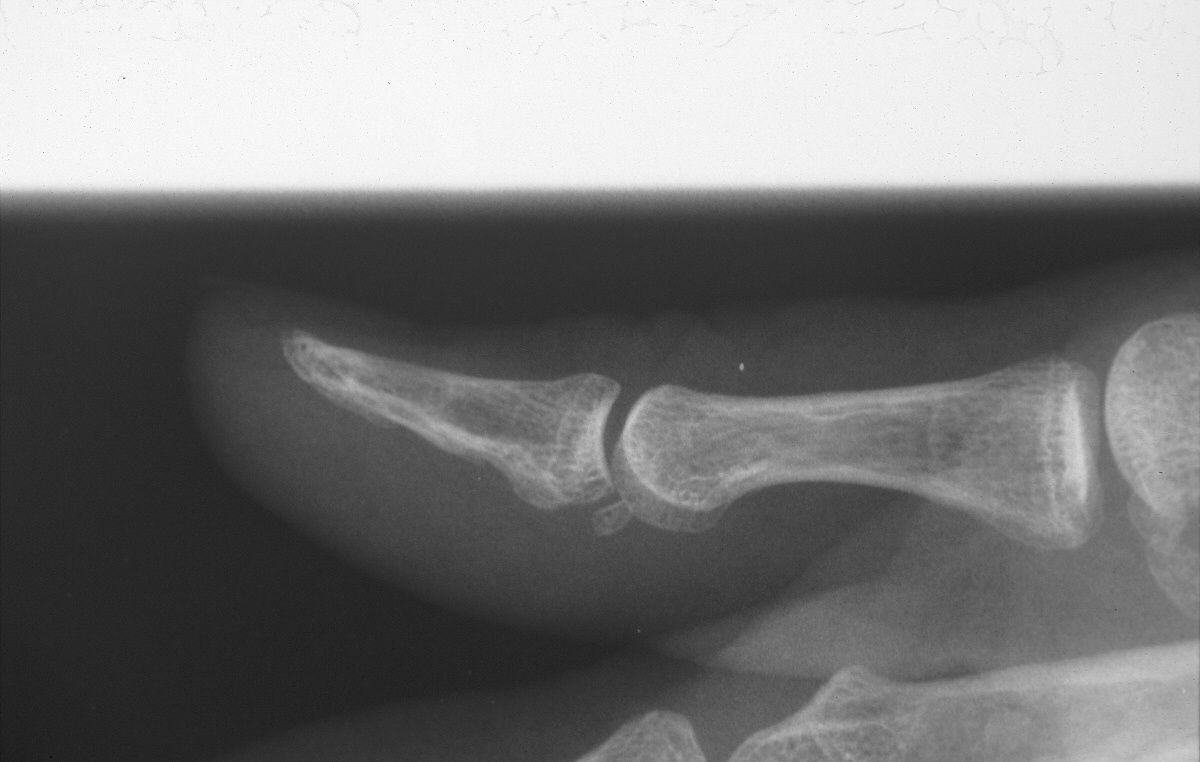

| Dorsal cortical impression

suggesting bilobed tumor. |